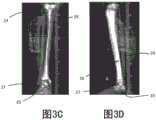

Fig. 3A and 3B are a-P (anterior-posterior) and lateral views of X-ray images of the tibia and talus.

Fig. 3C and 3D are a-P and side views, respectively, of the X-ray images of fig. 3A and 3B showing in X-ray images a virtual model of a tibia superimposed on the tibia and a virtual model of a talus superimposed on the talus.

Fig. 3A shows an X-ray image of thetibia 24 andtalus 25 from an a-P perspective. Fig. 3B shows an X-ray image of thetibia 24 andtalus 25 from a lateral perspective. Fig. 3C shows, in a-P views, atibia 24 overlapping atibial model 26 and atalus 25 overlapping atalar model 27. Fig. 3D shows, in a lateral perspective view, atibia 24 overlapping atibial model 26 and atalus 25 overlapping atalar model 27. The X-ray images of fig. 3A-3D may include the use of areference sleeve 28, as is known in the art, and thereference sleeve 28 may includemarkings 30, themarkings 30 being used to determine the scale of the image relative to the size of the bone.